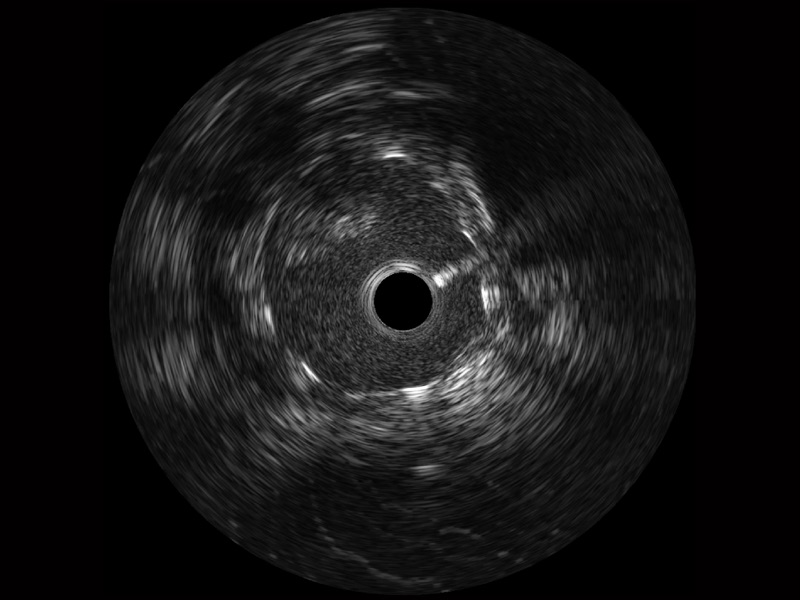

• 传统IVUS图像

对比传统IVUS导管成像,新葡的京集团8814检测站宽频IVUS图像的近场支架梁显影更细腻,远场中膜外血管仍清晰可辨,兼顾远中近,兼顾分辨力与穿透深度